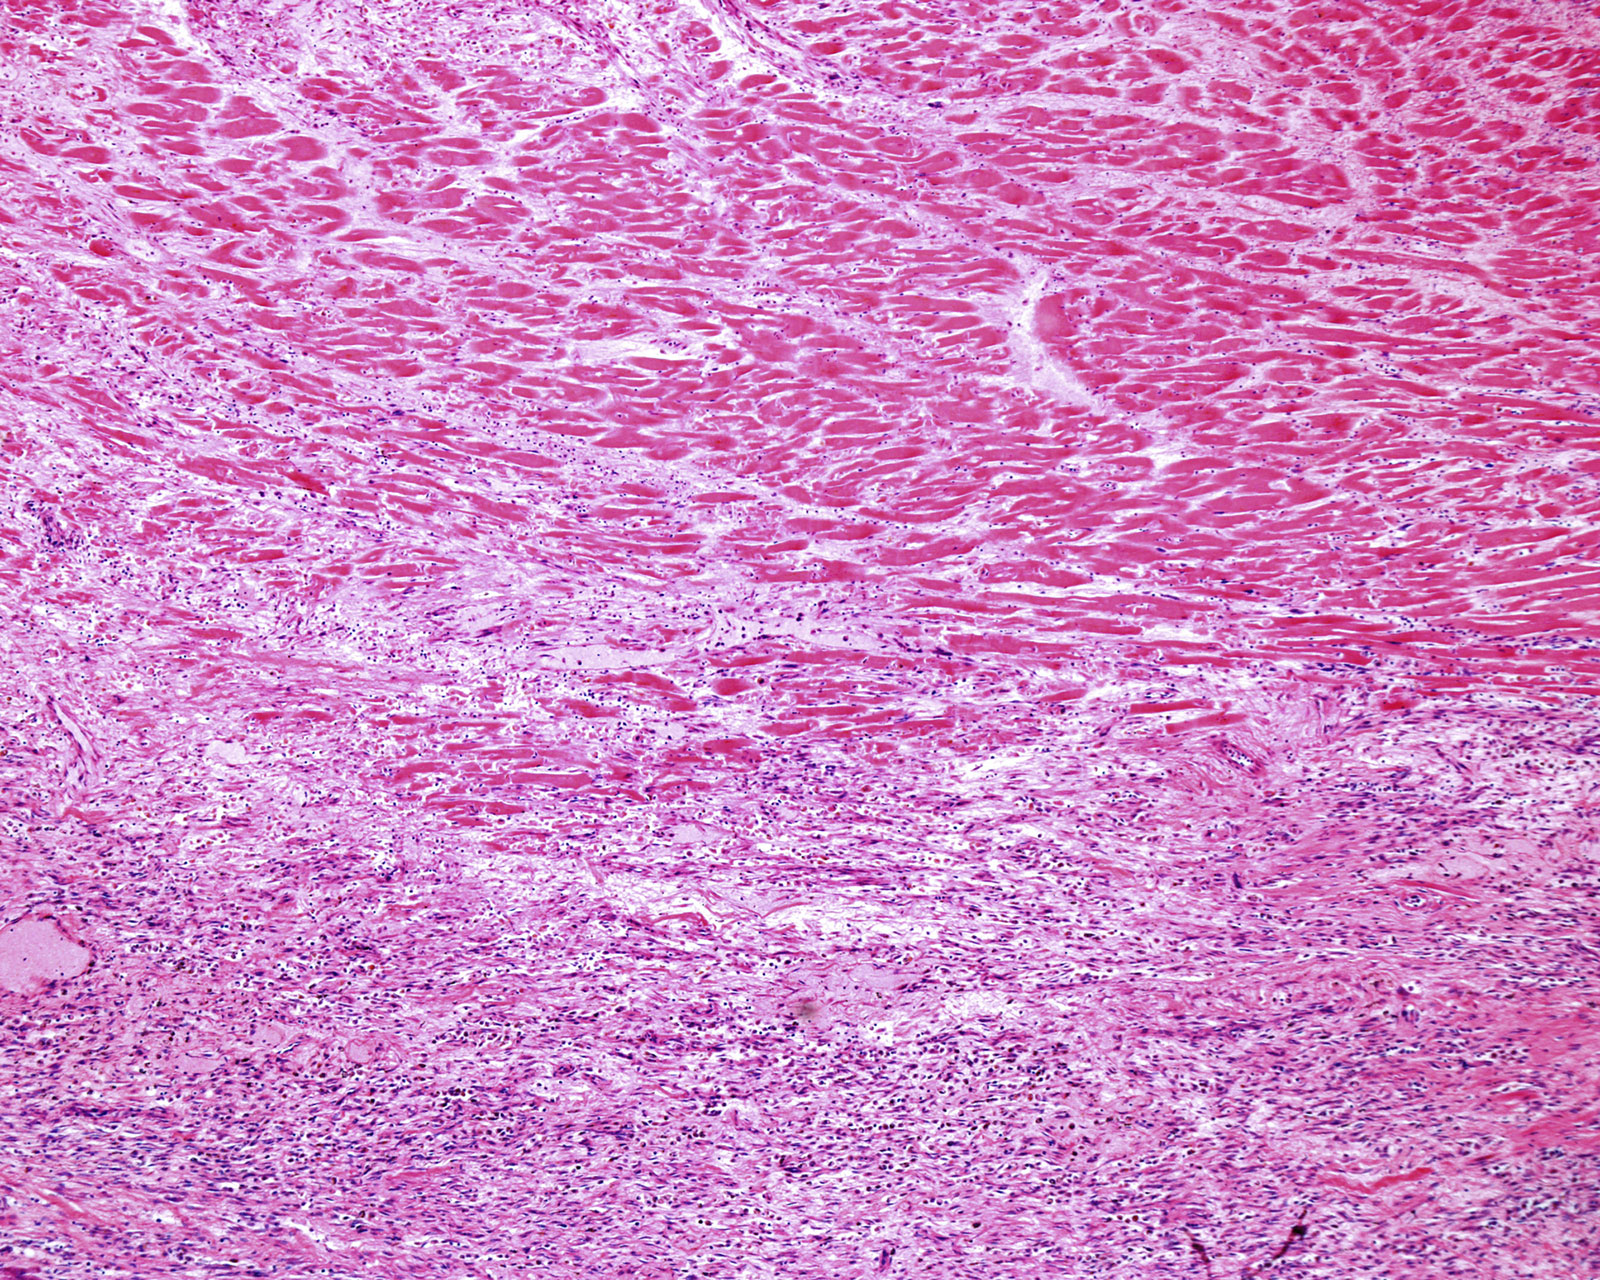

UC San Diego bioengineering professor Karen Christman has done groundbreaking work treating injured hearts with extracellular matrix, or ECM, a substance our bodies produce to give our tissues shape and form. She’s developed a gel made of ECM that can be administered in the aftermath of a heart attack. Once on scene, ECM both calms inflammation in damaged tissues and organizes itself into a structure that recruits new cells like those that form blood vessels. “That stimulates the heart to have less scar tissue and preserve more cardiac muscle,” Christman says.

Christman demonstrated that it’s safe to inject ECM directly into the heart with a catheter in a 2019 clinical trial. Patients who got the gel were eventually able to walk faster than those that didn’t, an indication that their hearts were working better. Now, she’s planning for a new clinical trial testing whether ECM can be delivered via a blood vessel that feeds the heart, which would enable doctors to administer it sooner and less invasively.